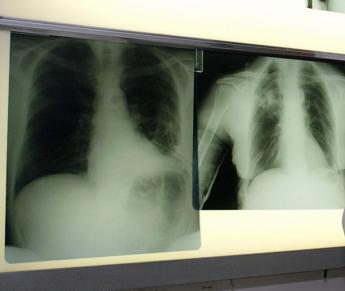

(Adnkronos) – Nasce, grazie alla collaborazione tra la Fondazione Irccs Istituto nazionale dei tumori (Int) di Milano, Msd Italia e la School of Management del Politecnico di Milano, un progetto finalizzato a revisionare e innovare i modelli organizzativo-gestionali dedicati al paziente con tumore al polmone, anche attraverso l'introduzione di nuove soluzioni digitali come la telemedicina, e in coerenza con le nuove linee di indirizzo nazionali e regionali. In Italia – si legge in una nota – il tumore al polmone è una delle neoplasie più diffuse e la prima causa di decesso per cancro dovuta all'elevata incidenza e alla difficoltà di una diagnosi precoce perché i sintomi si manifestano quando la malattia è già a uno stadio avanzato. L'iter diagnostico può essere inoltre molto complesso, soprattutto nel caso in cui il paziente presenti ulteriori comorbidità che ne inficiano le capacità di rispondere ai trattamenti. Risultano quindi fondamentali sia la definizione di processi di accesso in grado di raggiungere una diagnosi tempestiva della malattia, sia l'attuazione di un percorso di cura efficace e capace di rispondere alle esigenze del paziente e del proprio caregiver. L'annuncio della collaborazione con l'Irccs Int di Milano – Istituto che si posiziona al 19esimo posto nel mondo e quarto in Europa secondo la classifica dei migliori ospedali specializzati in oncologia redatta da Newsweek 2024 – è in linea con l'impegno di Msd nel mondo dell'oncologia dove da anni l'azienda, con la sua ricerca innovativa e i suoi oltre 1.700 clinical trial in corso, sta trasformando i paradigmi di cura nella lotta ai tumori. "L'Istituto ha una lunga e consolidata tradizione nella cura e nella ricerca, col fine ultimo di soddisfare le legittime aspettative dei pazienti – afferma Gustavo Galmozzi, presidente Int – Queste nostre peculiarità ci hanno portato a essere riconosciuti dal 2015 come Comprehensive Cancer Center di riferimento nazionale e internazionale sia per i tumori a maggiore incidenza sia per quelli rari che per quelli pediatrici, con offerta di prestazioni di ricovero e cura di alta specialità e di eccellenza, e Research & Teaching Hospital per le attività di ricerca pre-clinica, traslazionale, clinico-assistenziale, con una vocazione all'integrazione di ricerca scientifica, assistenza e formazione sul campo". Come osserva Nicoletta Luppi, presidente e amministratrice delegata di Msd Italia, "la diagnosi precoce, la presa in carico tempestiva del paziente e il suo ascolto sono passaggi strategici importanti che possono segnare la qualità del percorso terapeutico e gli esiti della malattia. A questi si aggiunge anche la possibilità di accedere ai farmaci innovativi, che in Italia fortunatamente, avviene grazie alla previsione nel nostro ordinamento di un Fondo ad hoc che ha contribuito in modo significativo a garantire un accesso ampio e tempestivo alle nuove molecole oncologiche nel nostro Paese. Un accesso che potrebbe essere ulteriormente migliorato se nel Fondo venissero inclusi anche i farmaci con innovatività condizionata". Nel dettaglio, la partnership sinergica con Irccs Int e School of Management del Politecnico di Milano per ciò che riguarda le attività di analisi, di misurazione dei risultati e di innovazione dei modelli di gestione dei percorsi di cura, anche in ottica di sanità digitale, prevede una revisione innovativa dei processi organizzativo-gestionali volta a: ottimizzare la presa in carico multidisciplinare, per raggiungere diagnosi e stadiazione rapide e garantire il trattamento più appropriato a tutti i pazienti eleggibili; valutare i benefici derivanti dall'introduzione di strumenti digitali, individuando le casistiche in cui tali soluzioni possono apportare maggior supporto alle attività cliniche. Inoltre, a individuare, attraverso un'analisi di benchmark con centri clinici nazionali e internazionali di rilievo, elementi migliorativi applicabili all'interno dell'Istituto e, infine, valorizzare best practice che contraddistinguono l'Istituto, da poter esportare in ulteriori processi di cura dell'Istituto e a livello regionale. "La sfida dell'innovazione organizzativa – sottolinea Carlo Nicora, direttore generale Fondazione Irccs Int – è una trasformazione radicale nella gestione dei processi di cura, nei sistemi di gestione delle performance, nelle competenze professionali degli operatori e nella loro cultura organizzativa. Rendere il sistema più efficace ed efficiente vuol dire impostare collaborazioni e quindi interventi capaci di impattare sui processi organizzativi innovando in modo creativo. Il modo in cui lavoriamo, capitale e tecnologia vengono combinati nell'ambito del modello organizzativo e possono fare la differenza. Innovare non significa solo disegnare nuove soluzioni, ma ottenere reali cambiamenti nella gestione delle nostre organizzazioni sanitarie che contribuiscono alla sostenibilità del sistema". Questo progetto "con la Fondazione Irccs Int e Msd Italia – precisa Paolo Locatelli, responsabile scientifico dell'Osservatorio Sanità digitale della School of Management del Politecnico di Milano – è un'importante occasione di cooperazione per il miglioramento del percorso di cura del paziente con tumore al polmone, in cui i 3 enti potranno mettere in gioco le proprie competenze e conoscenze a beneficio dei pazienti. Nel corso degli ultimi anni il gruppo di lavoro del Politecnico di Milano coinvolto nella collaborazione ha acquisito sia una crescente expertise rispetto all'ottimizzazione dei processi gestionali in sanità, che un'ampia conoscenza del percorso di cura del paziente con tumore al polmone, grazie alle diverse collaborazioni condotte in tale ambito". —salutewebinfo@adnkronos.com (Web Info)